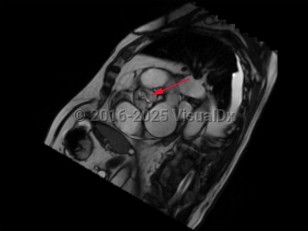

Aortic stenosis (AS) is the narrowing of left ventricular outflow through the aortic valve. It is the most prevalent cause of ventricular outflow obstruction, and it is increasing in prevalence as the population ages and life expectancy increases. While patients are generally asymptomatic in the presence of mild outflow obstruction, exertional dyspnea, chest discomfort, fatigue, dizziness, and syncope develop as the degree of obstruction progresses.

Contributing etiologies include calcification of the aortic valve cusps (most common in the elderly population), congenital abnormalities (ie, bicuspid aortic valve), rheumatic fever, chest radiotherapy, endocarditis, and alkaptonuria. Potential complications include heart failure, cardiac arrhythmias, infectious endocarditis, pulmonary hypertension, excessive bleeding, stroke, and other embolic events.

There is no known medical therapy available to delay progression of AS. Patients should be monitored carefully with serial clinical evaluations and echocardiography in order to determine if and when aortic valve replacement is needed, which may be performed by surgical aortic valve replacement or transcatheter aortic valve replacement (TAVR), also known as transcatheter aortic valve implantation (TAVI). Prolonged or intense physical activity and competitive sports should be avoided in patients with severe AS.